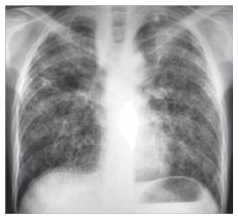

Paciente do sexo masculino, 34 anos, procedente do Ceará, refere dispneia que se intensificou há dois anos. Refere que há 20 anos trabalha no interior do Ceará cavando cacimbas (poço de água potável). Realizado exame radiológico (ilustrado a seguir), que evidenciou infiltrado reticulonodular e pequenos nódulos difusos que poupam os seios costofrênicos.

A hipótese diagnóstica mais provável é a